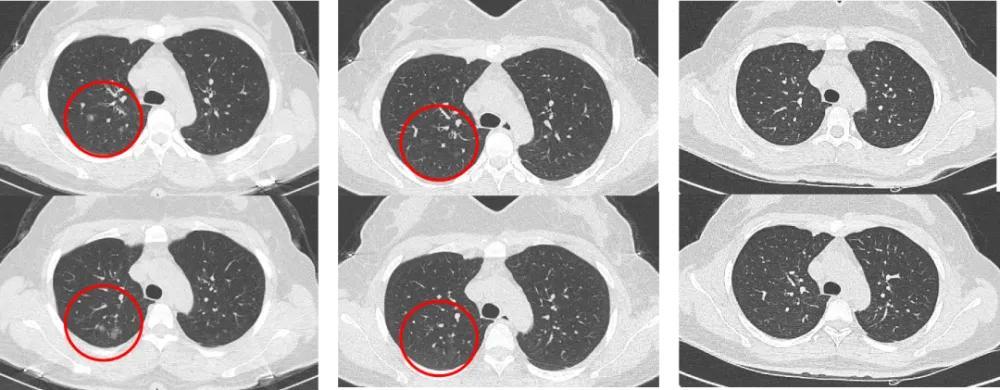

像32岁张先生这样的肺部CT体检报告,大家肯定不会陌生

虽然我们医生反复强调肺结节大部分都是良性的, 但是对于普通老百姓来说,面对报告单中(119/257img)、(105/257img)等这些这么大数字,怎么都会看着有点慌 ,因为人类面对未知就会有天生恐惧。

那么CT报告单上的(119/257img)、(105/257img)到底是什么意思?如果两次拍片,查出来数字不一样,是不是说明结节有问题?

这主要是因为拍CT就跟我们切洋葱一样,是一层一层切的拍的,一个人拍个肺部CT,往往会有成百上千张图像。

在这么大量的图像里面,假如我们不标注位置,那医生要找到那几个毫米大小的结节是非常困难的,因此,主要是便于我们医生在众多的CT图像上找到这个结节。